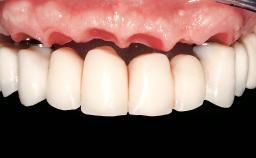

Immediate Loading of Eight Implants in the Maxilla and Six Implants in the Mandible and Final Restoration with Three-Unit and Four-Unit FDPs

SAC Level Complex

Defining Characteristics Fully edentulous upper jaw to be rehabilitated with an implant-borne fixed dental prosthesis

Loading Protocol Immediate